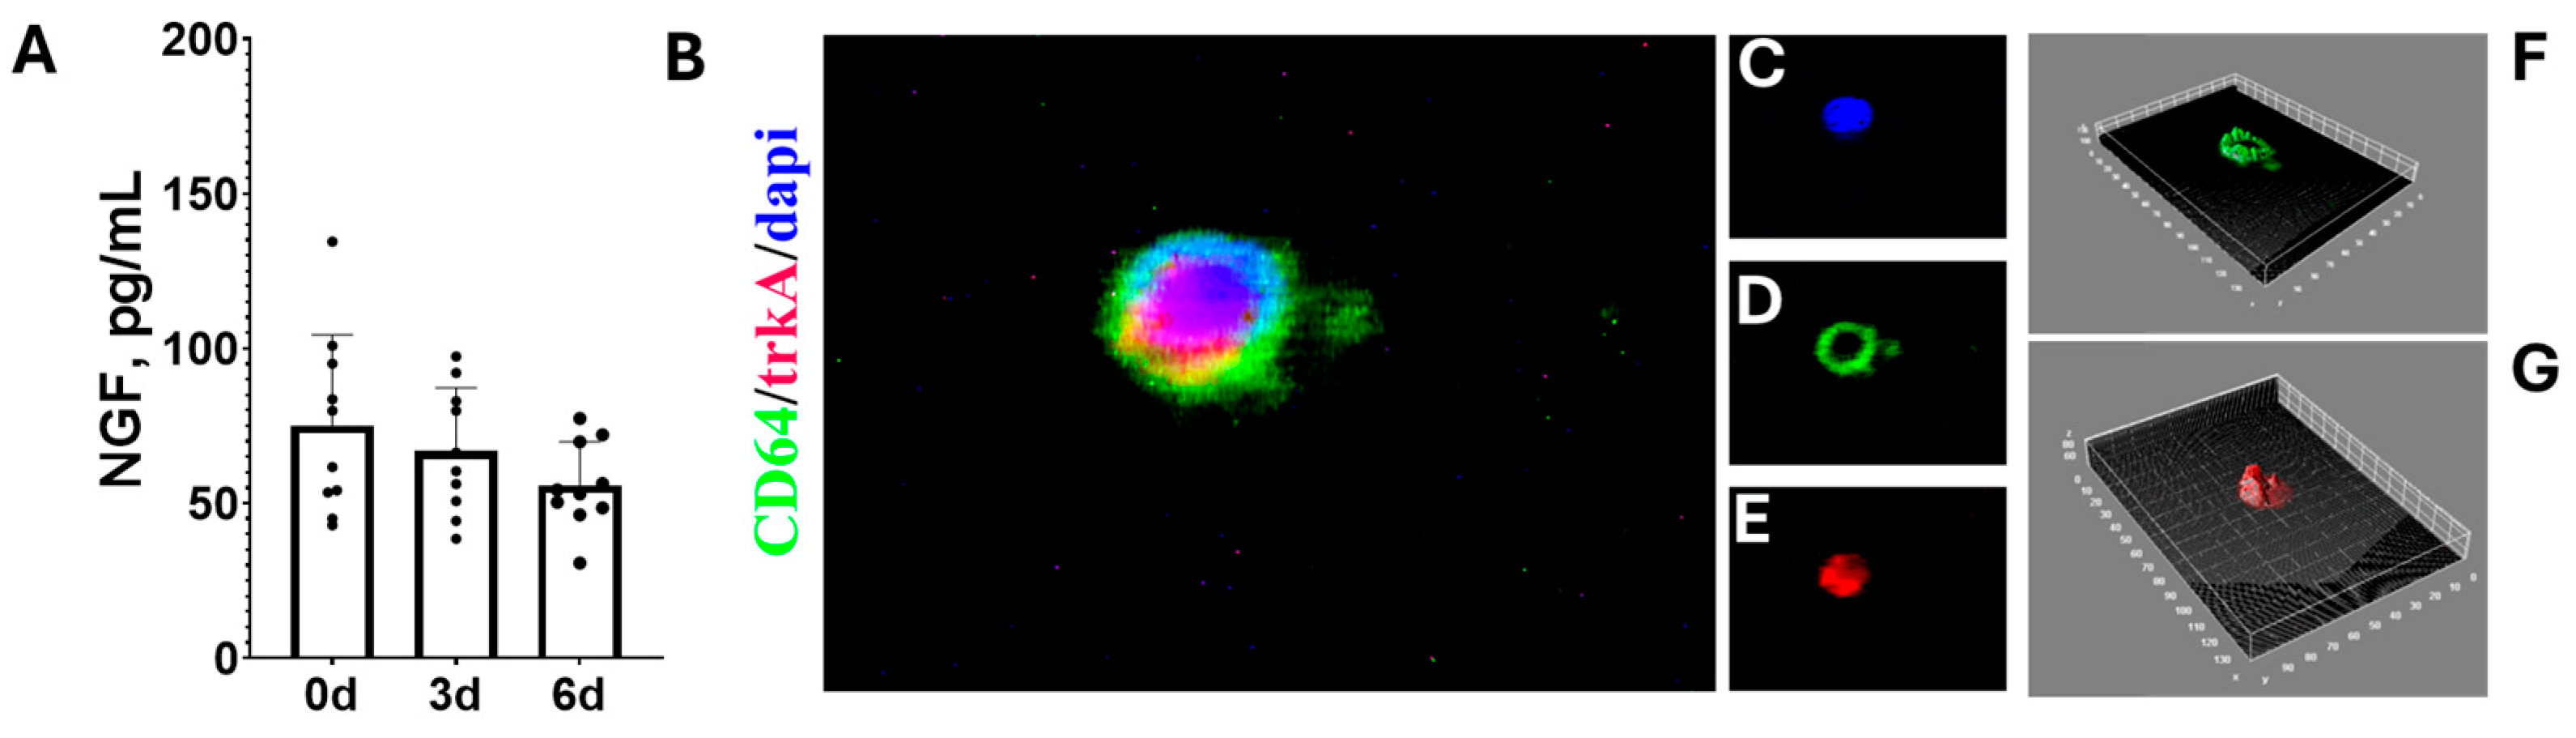

3.4. Hyalocyte-Enriched Cultures Express Growth Factors Retaining Their Initial Pathological Phenotype in 3-D Cultures and Express the NGF Pathway